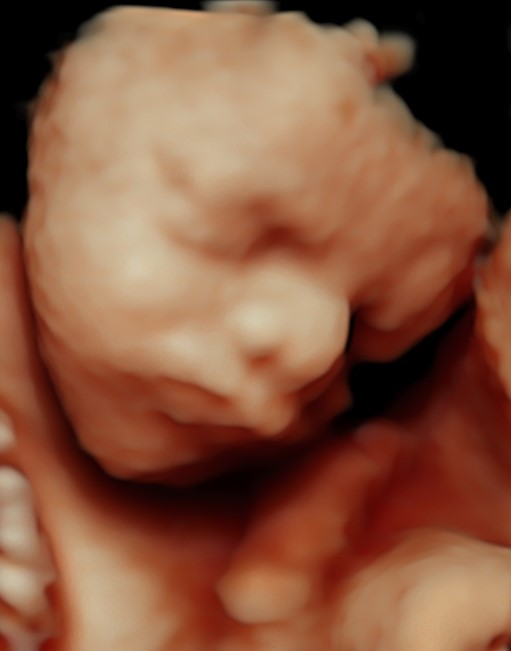

Monmouth County’s First 4D/5D/HD Live Ultrasound Studio

4D/5D/HD Ultrasound Gallery

Gallery